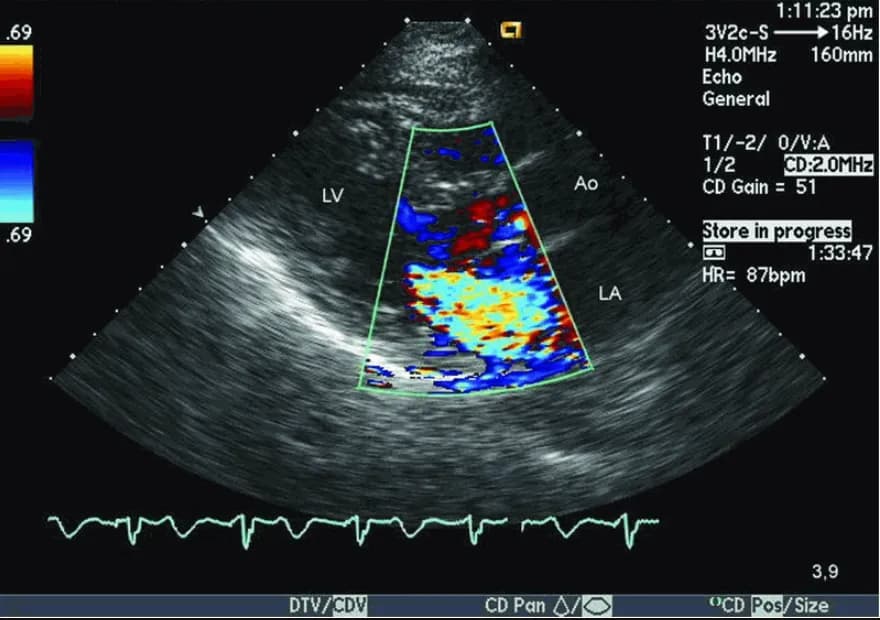

Hở van tim 2 lá là bệnh gì? Nguyên nhân, triệu chứng, cách phát hiện

Hở van tim 2 lá là tình trạng van tim bị hở, gây ảnh hưởng đến dòng máu trong tim. Nguyên nhân có thể do thấp tim, thoái...